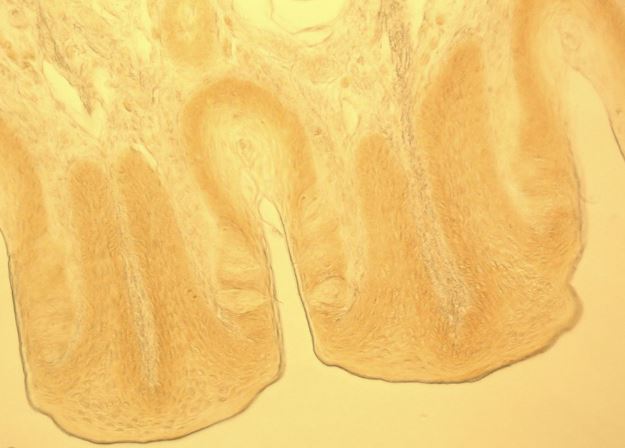

兔子味蕾斷面,相差顯微鏡

兔子味蕾斷面,微分干涉對比顯微鏡

兔子味蕾斷面,明場顯微鏡